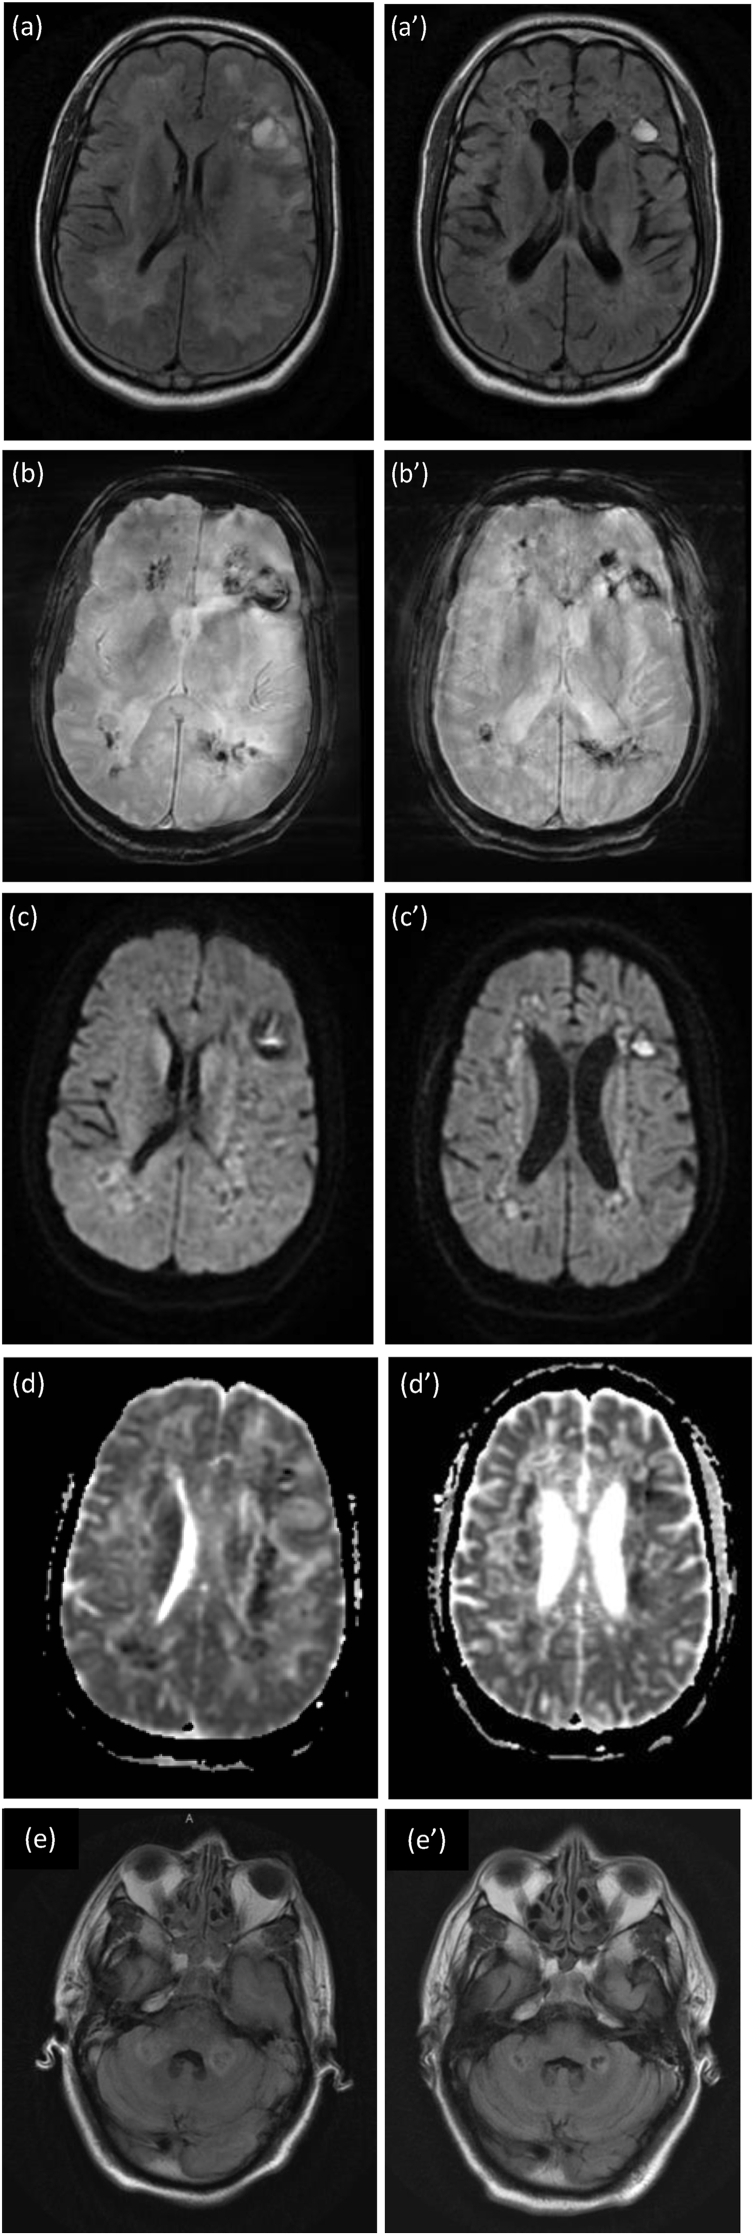

A repeat unenhanced CT brain on day 47 of admission showed no evidence of acute infarction, or intra-axial or extra-axial haemorrhage. Mild generalised involutional changes and small vessel disease were present on the scan. A repeat MRI of his brain was performed on day 60 (5 weeks after the initial imaging scan) to assess for changes and improvement. The MRI findings were still compatible with haemorrhagic leukoencephalitis. The appearances were less marked in comparison with the initial MRI. It also illustrated evidence of leukoencephalitis involving the cerebellum and the pons, with no evidence of haemorrhage within them (Fig. 2). An electroencephalography (EEG) as follow-up on day 65 was performed. EEG was diffusely slow and poorly responsive in keeping with a diffuse encephalopathy or encephalitis with no epileptiform discharge.

Fig. 2.

Magnetic Resonance Imaging (MRI) of the brain.

Left Column, Initial brain MRI:(a) Axial fluid-attenuated inversion recovery (FLAIR), (b) Susceptible-weighted imaging (SWI), (c) Diffusion-weighted imaging (DWI), (d) Apparent Diffusion Coefficient (ADC) sequences, and (e) view of cerebellum involvement in Axial T2 fluid-attenuated inversion recovery (FLAIR) are demonstrated here.

Increased symmetrical FLAIR signal throughout the white matter. Diffuse haemosiderin staining throughout the white matter and the genu of the corpus callosum. There are also some cystic haemorrhagic areas containing a fluid-blood level within both cerebral hemispheres. There are some areas of restricted diffusion within the white matter, but this signal change is unreliable owing to the presence of acute haemorrhage.

Right Column, Repeat Follow-Up MRI on Day 60. (a’) Axial fluid-attenuated inversion recovery (FLAIR), (b’) Susceptible-weighted imaging (SWI), (c’) Diffusion-weighted imaging (DWI), (d’) Apparent Diffusion Coefficient (ADC) sequences, and (e’) view of cerebellum involvement in Axial T2 fluid-attenuated inversion recovery (FLAIR) are demonstrated here.

Extensive abnormal signal throughout the white matter bilaterally with haemorrhage compatible with haemorrhagic leukoencephalitis. the appearances are slightly less marked compared with the previous examination. There is evidence of leukoencephalitis involving the cerebellum and the pons, though there is no evidence of haemorrhage within the pons or cerebellum.

Findings at MRI brain were suggestive of underlying acute haemorrhagic leukoencephalitis (AHLE) (Fig. 2).